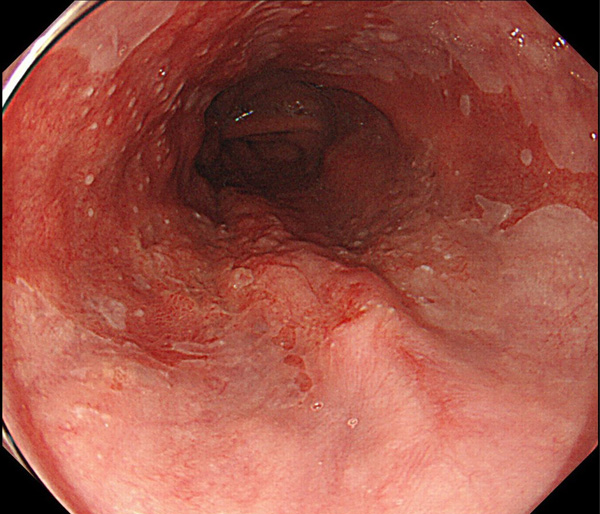

内視鏡所見と病理組織像の1対1対応が可能な症例を公募いたします。主にLSBEに発生した早期癌(HGDを含む)を対象としますが、興味深い症例であればSSBE癌でも結構です。採否は世話人へご一任ください。

特に、本邦では極めて稀なlong segment Barrett’s esophagus(LSBE)から発生した早期癌は、診断に難渋する場合も多く、欧米ではランダム生検による検出が標準的とされています。背景のBarrett食道もろとも全体を内視鏡切除+ラジオ波焼灼する欧米と異なり、ESDで内視鏡的な局所切除が基本の本邦では、存在診断+範囲診断(特に水平)を的確に行うことが不可欠です。

そのためには、一流の病理医による組織学的診断とエキスパート内視鏡医による拡大内視鏡像との一対一対応を徹底的に行うことで、『本来、見えないであろう拡大所見の先にある組織構築像が診えてくる』所まで内視鏡診断レベルを上げていく必要があります。その実現には、一対一対応を追究した症例(特にLSBE発生例)1例でも多く経験するしかありません。本研究会でBarrett食道腺癌(LSBE発生早期病変)を共に学び、拡大内視鏡像の一歩先を診るスキルを習得しましょう!一人でも多くの皆様のご参加をお待ちしています。

私は、Barrett食道癌はHGDも含め、内視鏡による存在診断、範囲診断が可能と信じて来ました。しかし最近、NBI拡大観察を併用しても側方範囲診断が不可能なLSBE症例を経験しました。診断技術を向上させるためには、多くの症例を診るしかありません。そこで、Barrett食道に造詣の深い先生方に世話人をお願いし、Barrett食道研究会を立ち上げることに致しました。全国からLSBE症例を集め、内視鏡的、組織学的診断に迫りたいと思います。皆様のご参加をお待ち致します。